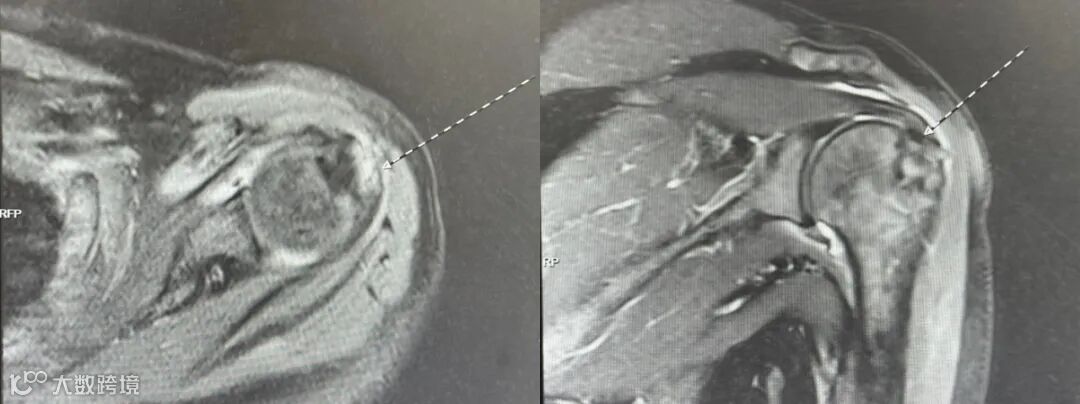

MRI(磁共振):金标准,能清晰显示肌腱撕裂的位置、大小和程度